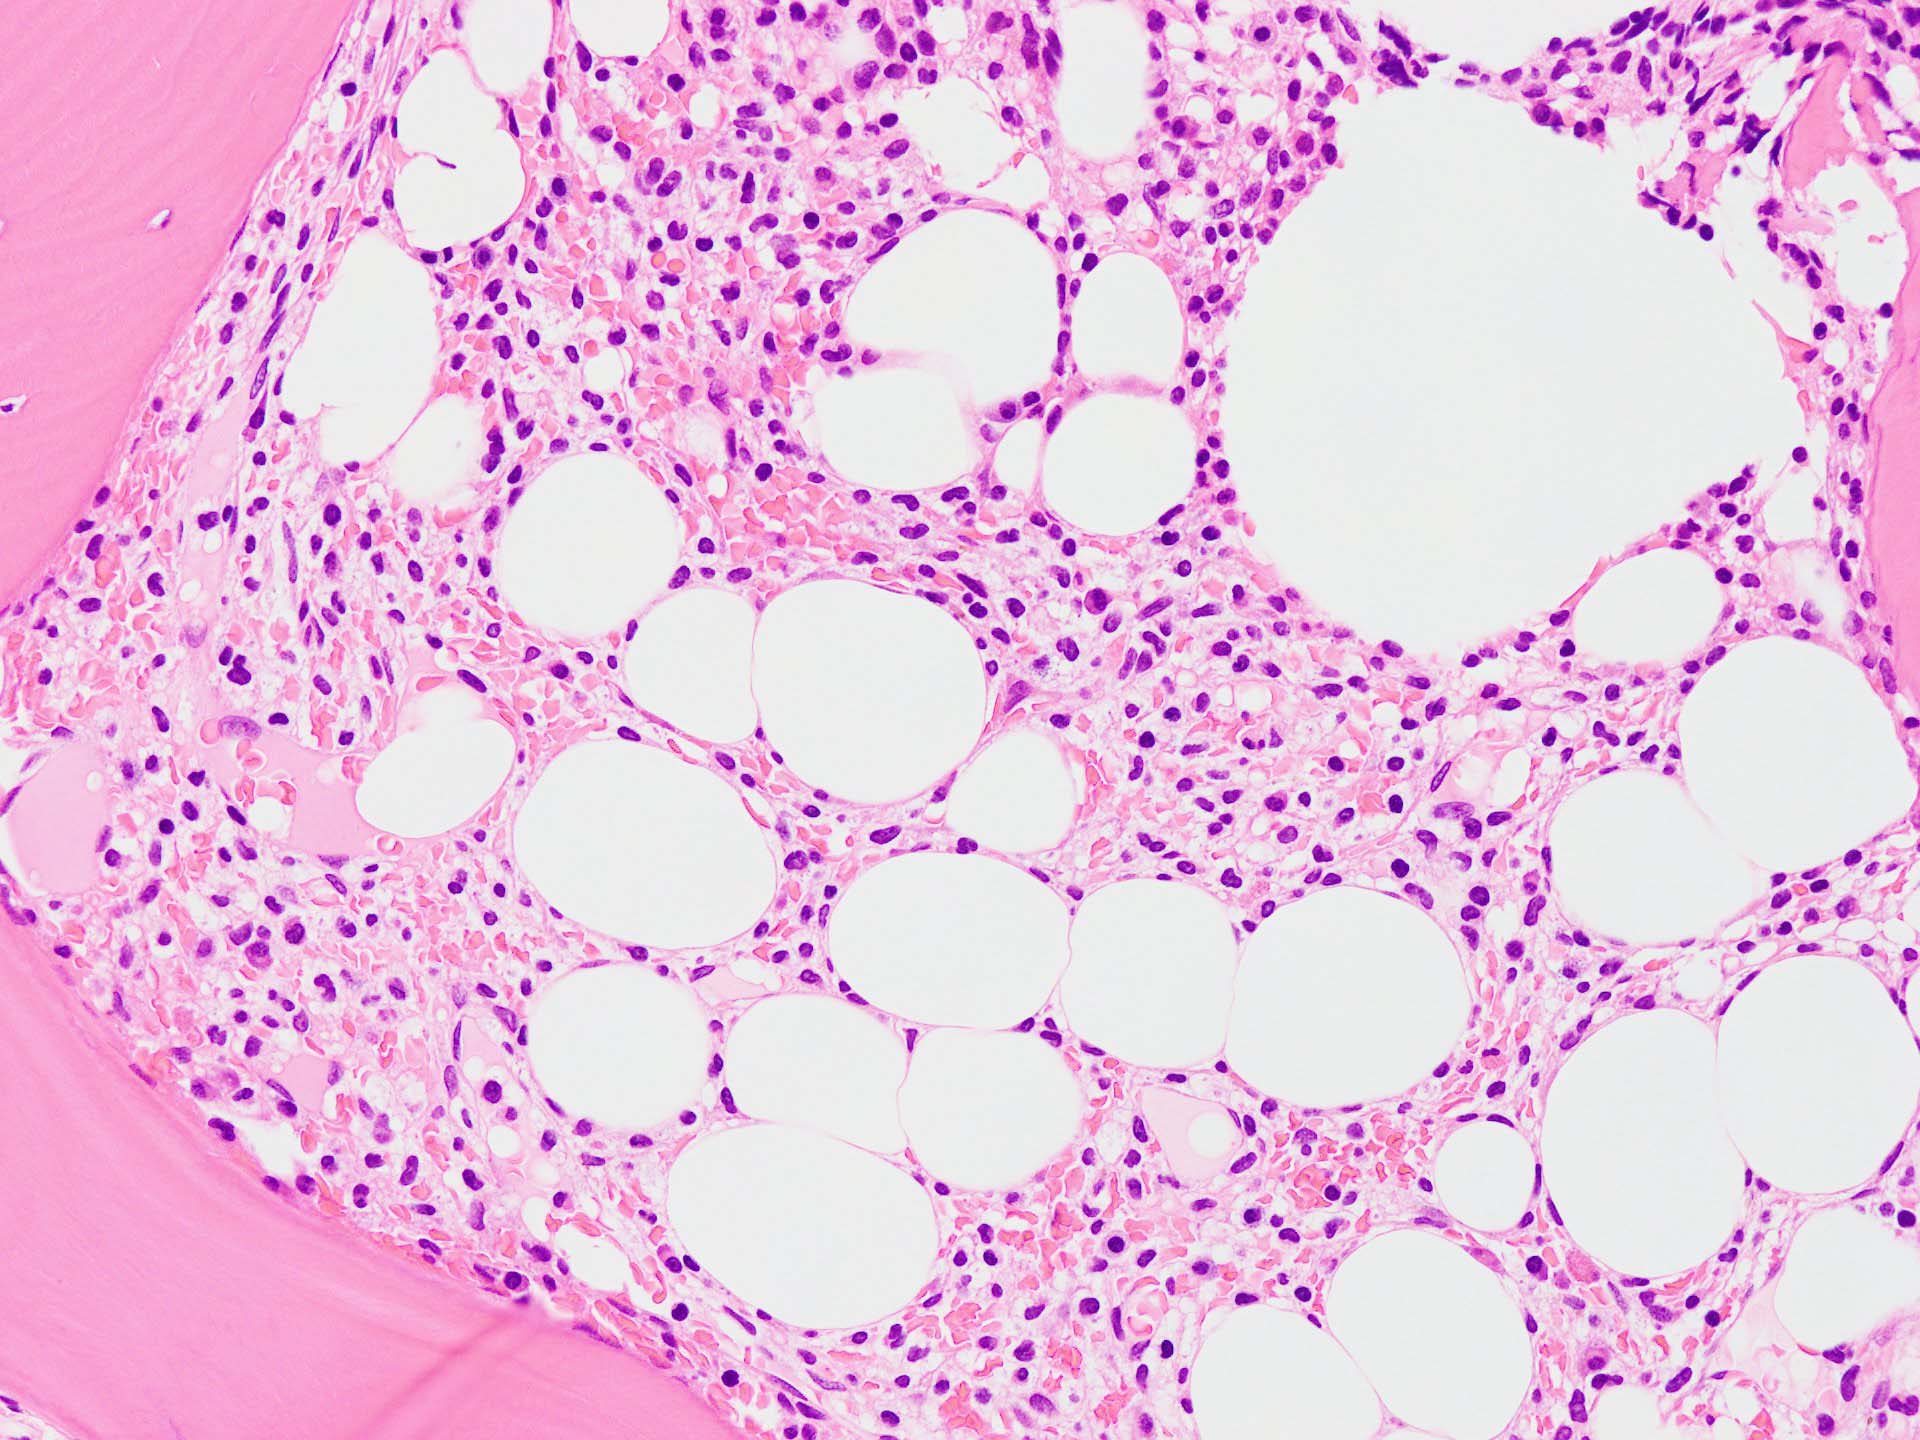

ASD-Giemsa陰性の細胞がシート状に増殖する. 核はクロマチン濃染, 核小体は不明瞭.類円形, 卵円形, くびれを持つ多稜形核, 長円形いびつで屈曲した核, など多彩. 細胞質は淡清色調, 広く淡明. 赤芽球血島は幼若赤芽球のみで形成される異形成像を示す. やや離れて成熟赤芽球が疎な集簇を示す.

Ag染色では, 疎な弾性線維が増生し,増殖細胞を小胞巣状に分画するいわゆる「lymphomatoid pattern」を呈する. 本例では, Mgkに異形成所見がある.